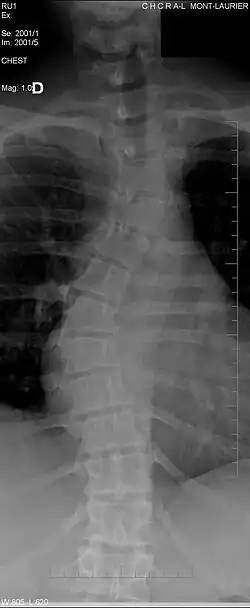

Le dos humain se compose de sept vertèbres cervicales, douze vertèbres thoraciques (ou dorsales), cinq vertèbres lombaires (ou lombales), cinq vertèbres sacrales et le coccyx.

Toutes les vertèbres (excepté les premières vertèbres cervicales, les sacrales et les coccygiennes) sont séparées les unes des autres par un disque intervertébral. Les centres des vertèbres sont empilés, ce qui fait que leurs arcs forment un tube par lequel la moelle spinale passe. À partir de la moelle spinale, des nerfs passent entre les vertèbres, pour innerver par exemple les jambes et les bras.